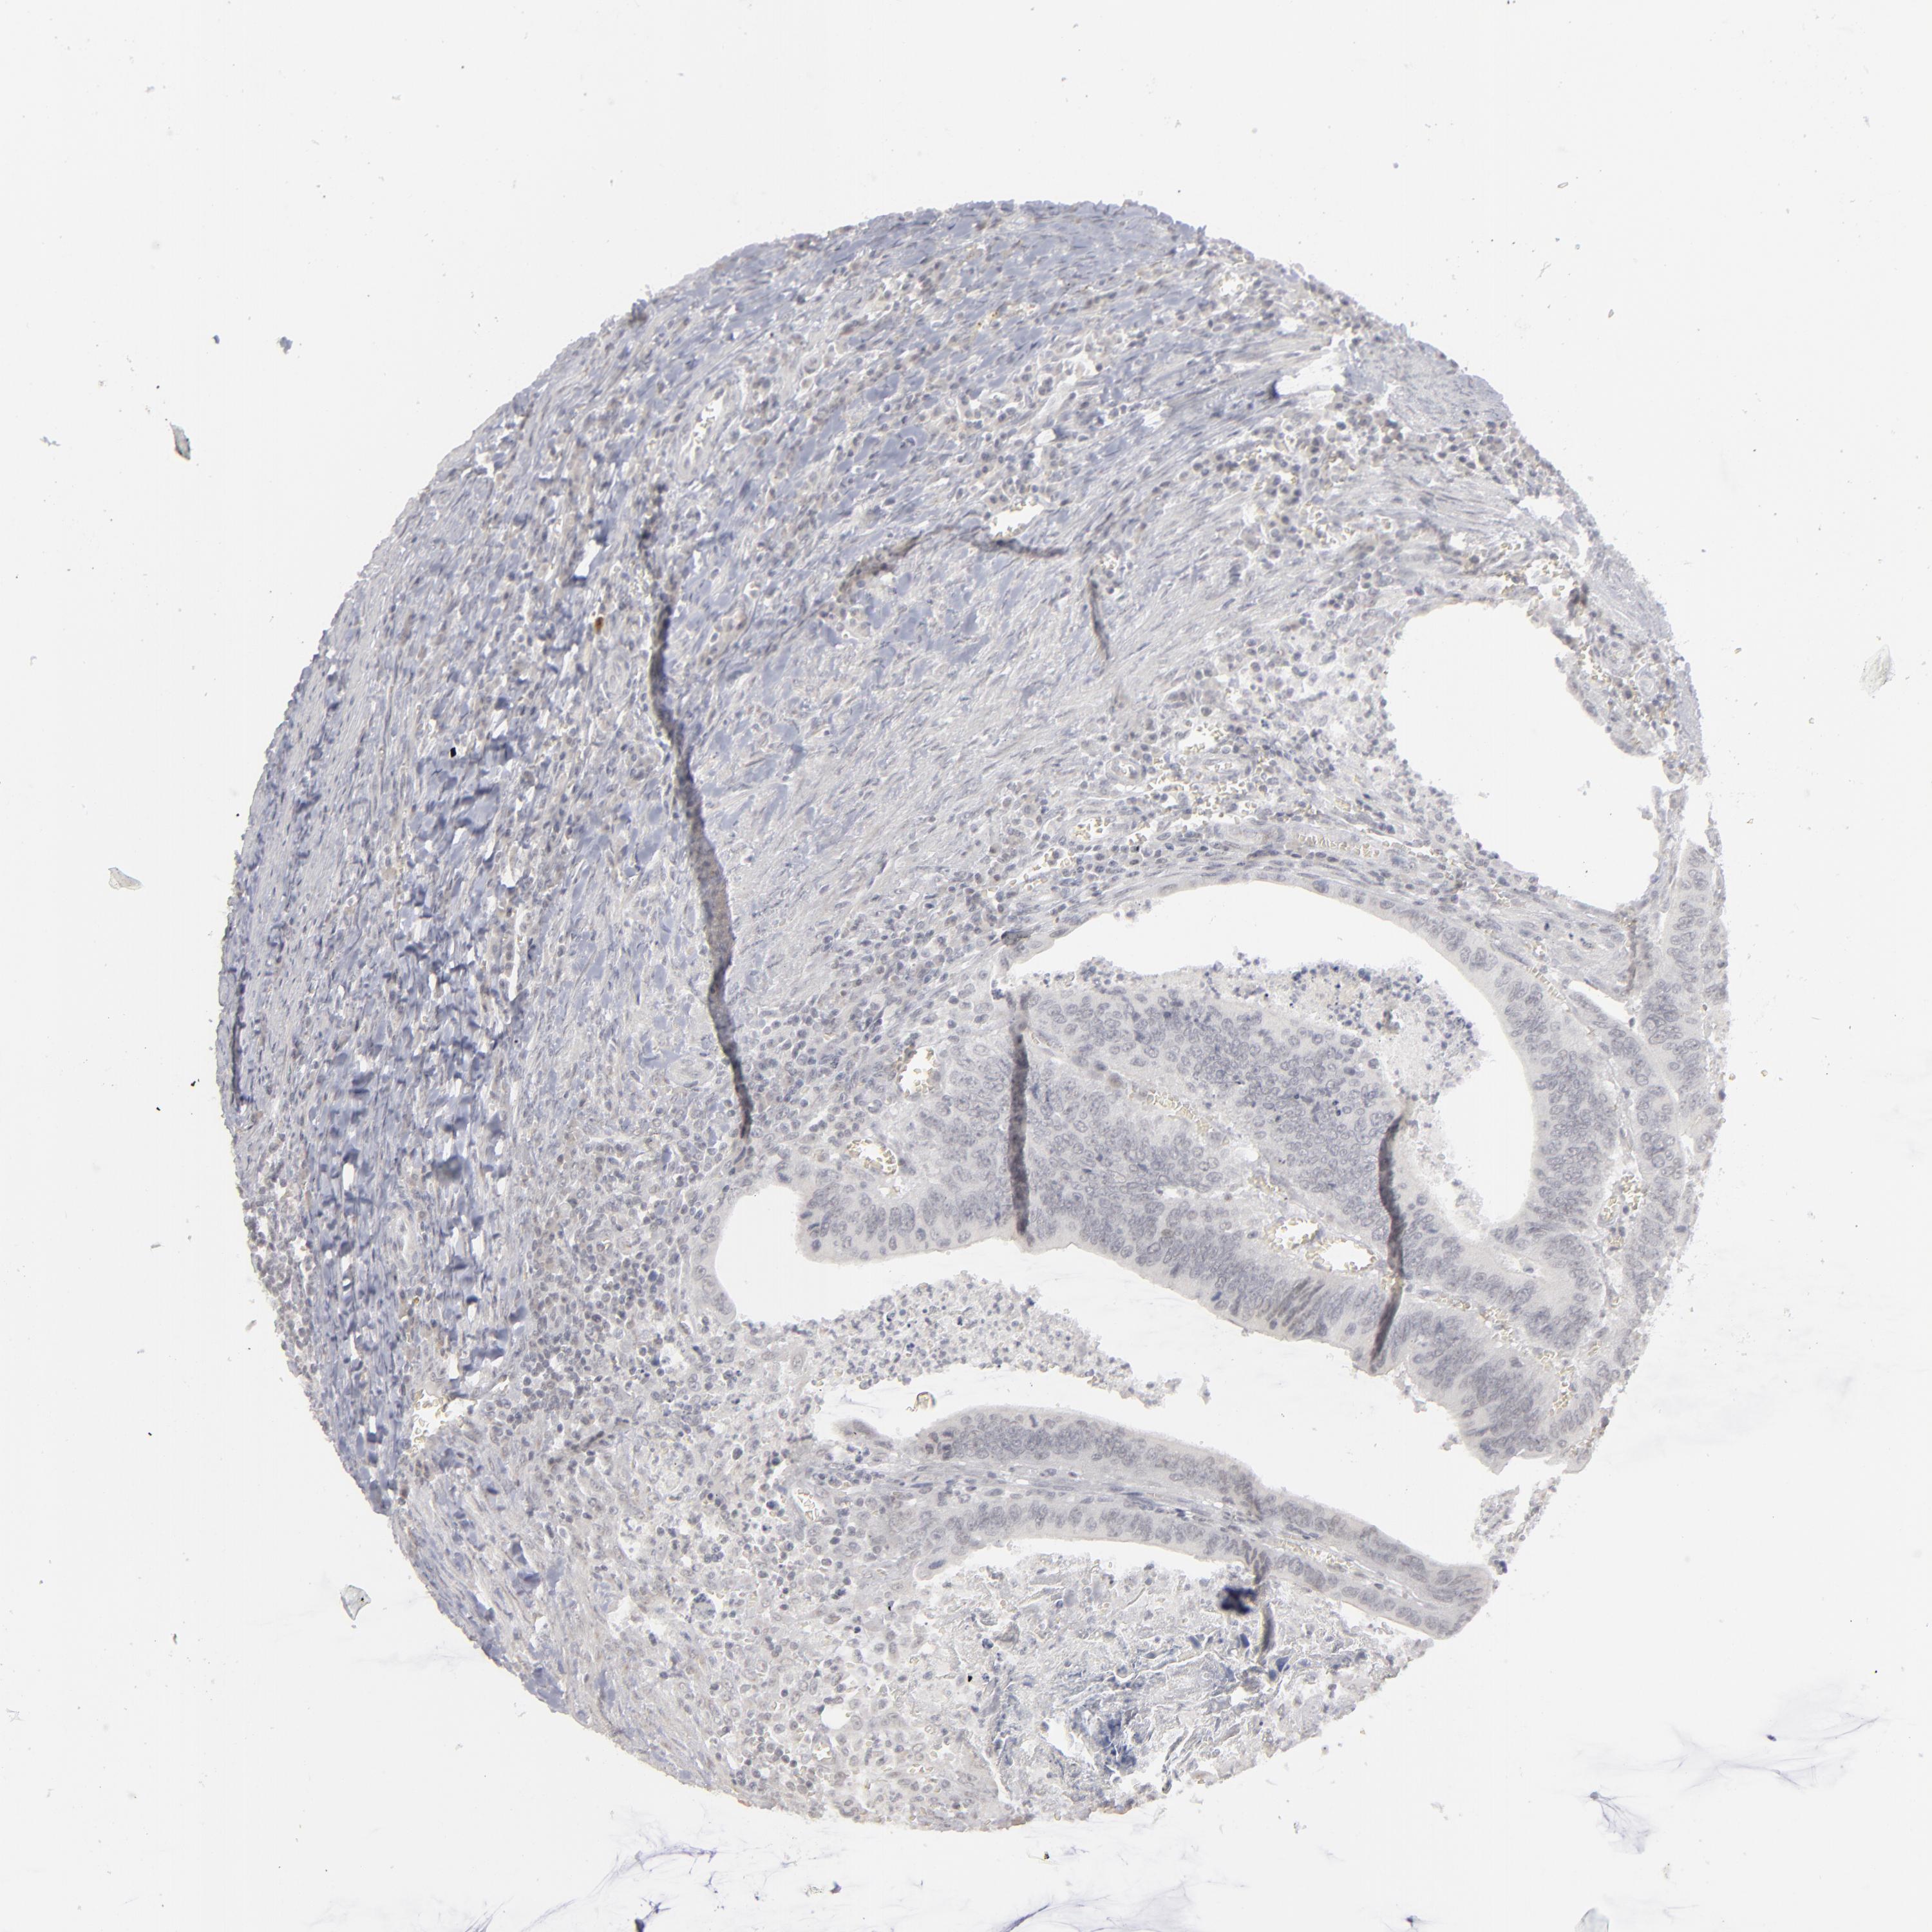

CANCER COLORECTAL CANCER Show tissue menu

Colorectal cancer

Human cancer

Colon adenocarcinoma